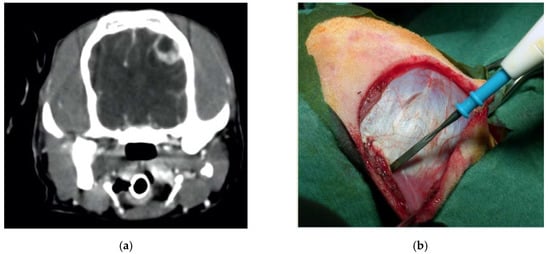

Dog, female, crossbreed, six years old, 14 kg, who suffered from seizures due to a suspected left intracranial parietal meningioma. She underwent a lateral rostro tentorial craniotomy with the piezoelectric bone scalpel. No dura mater sinus was present. The scalpel was essential in sparing the underling dura and brain. The tumor was completely removed, and recovery was complete, without complications (Figure 6).

Figure 6.

Preoperative contrast-enhanced CT scan, showing a suspected left parietal meningioma (a). Intraoperative pictures showing the initial steps of the craniotomy (b). The bone flap was cut with piezoelectric scalpel and an angled large saw tip (OT7, Osteotomy Tips Kit, Mectron Medical Technology, Genoa, Italy) (c,d). The dura was completely preserved (e). En bloc removal of meningioma (f). Postoperative CT scan performed at six-month follow-up, showing the sharpness of the edges of the craniotomy. No osteosclerosis or bony resorption was evident (g).